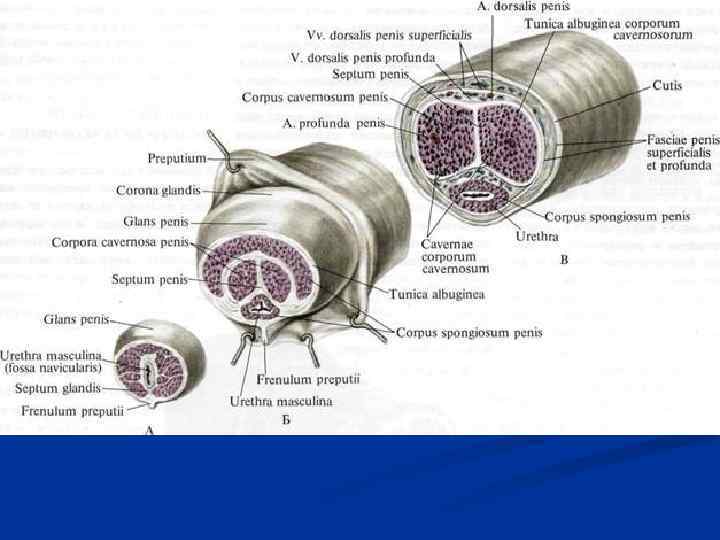

Половой член покрыт кожей (1), cutis которая на нижней поверхности образует шов, raphe penis. В переднем отделе выраженная кожная складка – крайняя плоть (2), preputium penis формирующая препуциальный мешок, saccus preputium. Внутренняя поверхность крайней плоти соединена с головкой (3), glans penis уздечкой крайней плоти, frenulum preputii в области ладьевидной ямки мочеиспускательного канала (4), fossa navicularis uretrae. В полость препуциального мешка железы крайней плоти, glandulae preputialis выделяют смегму (препуциальный жир).

Половой член покрыт кожей (1), cutis которая на нижней поверхности образует шов, raphe penis. В переднем отделе выраженная кожная складка – крайняя плоть (2), preputium penis формирующая препуциальный мешок, saccus preputium. Внутренняя поверхность крайней плоти соединена с головкой (3), glans penis уздечкой крайней плоти, frenulum preputii в области ладьевидной ямки мочеиспускательного канала (4), fossa navicularis uretrae. В полость препуциального мешка железы крайней плоти, glandulae preputialis выделяют смегму (препуциальный жир).